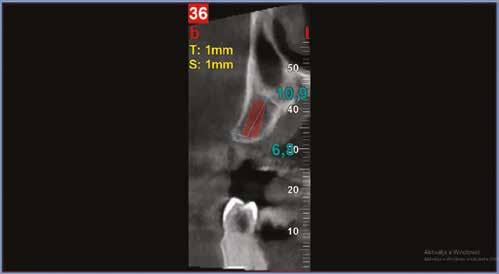

Az 50 éves nőpáciens az alsó és felső állcsont területén egyaránt panaszt (fájdalom, ráharapási érzékenység) okozó, harmadfokban mozgatható fogak miatt jelentkezett rendelőnkben. Az általános anamnézisben említést érdemlő betegség, műtét nem szerepelt. Az elvégzett klinikai és radiológiai vizsgálatok (1–2. ábra) alapján fogai reménytelen parodontális státusúnak bizonyultak, hosszú távon sem megtartásuk, sem protetikai célú felhasználásuk nem volt lehetséges. A parodontális prognózis a fogak eltávolításának abszolút indikációját jelentette. Ezáltal mindkét állcsontban teljes foghiány kialakulásával kellett számolnunk. A protetikai szemléletű, „visszafelé” tervezés elveit követtük a hosszú távú funkcionális, esztétikai siker és szöveti stabilitás elérése érdekében: mindkét állcsontban overdenture típusú fogpótlás készítése mellett döntöttünk. A megfelelő implant-protetikai rehabilitáció alapja az implantátumok megfelelő pozicionálása. A korábbi parodontális kórfolyamat következtében a processus alveolarisokat érintő eredendő csontdeficittel kellett számolnunk, amelyet tovább súlyosbíthatott volna a hagyományos extrakciós technikát követő involúciós atrófia. Ezért a páciens kivizsgálása és megfelelő előkészítése után a fog eltávolításával egy időben PRF

27 VI. ÉVFOLYAM – 2023. 4. SZÁM

Sticky Tooth segítségével kivitelezett alveolus prezerváció mellett döntöttünk, a megfelelő csontos és mukogingivális gyógyulás minőségi és mennyiségi elősegítése érdekében. A PRF készítmény mennyiségét, minőségét, kezelhetőségét és hatékonyságát jelentősen befolyásolják a páciens laborértékei, ezért kezelési protokollunk szerint a műtétet megelőzően minden esetben laborvizsgálatot végzünk (hemoglobin: 134 g/liter, hematokrit: 0,43, fehérvérsejt: 6,6 G/liter, CRP: 13,60 mg/liter, vércukor: 6,2 mmol/liter, összkoleszterin: 7,00 mmol/liter, triglicerid: 1,08 mmol/liter, HDL koleszterin 2,57 mmol/liter, LDL koleszterin 1,12 mmol/liter), D3 vitamin: 117,5 nmol/liter).

A gyógyulási időszakot követően a csontos gyógyulás ellenőrzése és az implantáció tervezése céljából állcsonti CT-felvételt készítettünk. A CT-felvételen tökéletes csontos gyógyulást észleltünk, az alveoláris csont volumene

Fergeteges

teljes mértékben megtartott, a vertikális augmentáció a tervezettnek megfelelő eredményű volt (13–15. ábra), a klinikai kép is ennek megfelelően alakult, optimális menynyiségű keratinizált ínnyel és azt adekvát sebészi technika eredményeképpen megtartott vesztibulummal (16–17. ábra). Az alsó és felső állcsontba 4-4 darab Bredent COPA Sky implantátumot ültettük, D1-D2 csontminőség mellett,